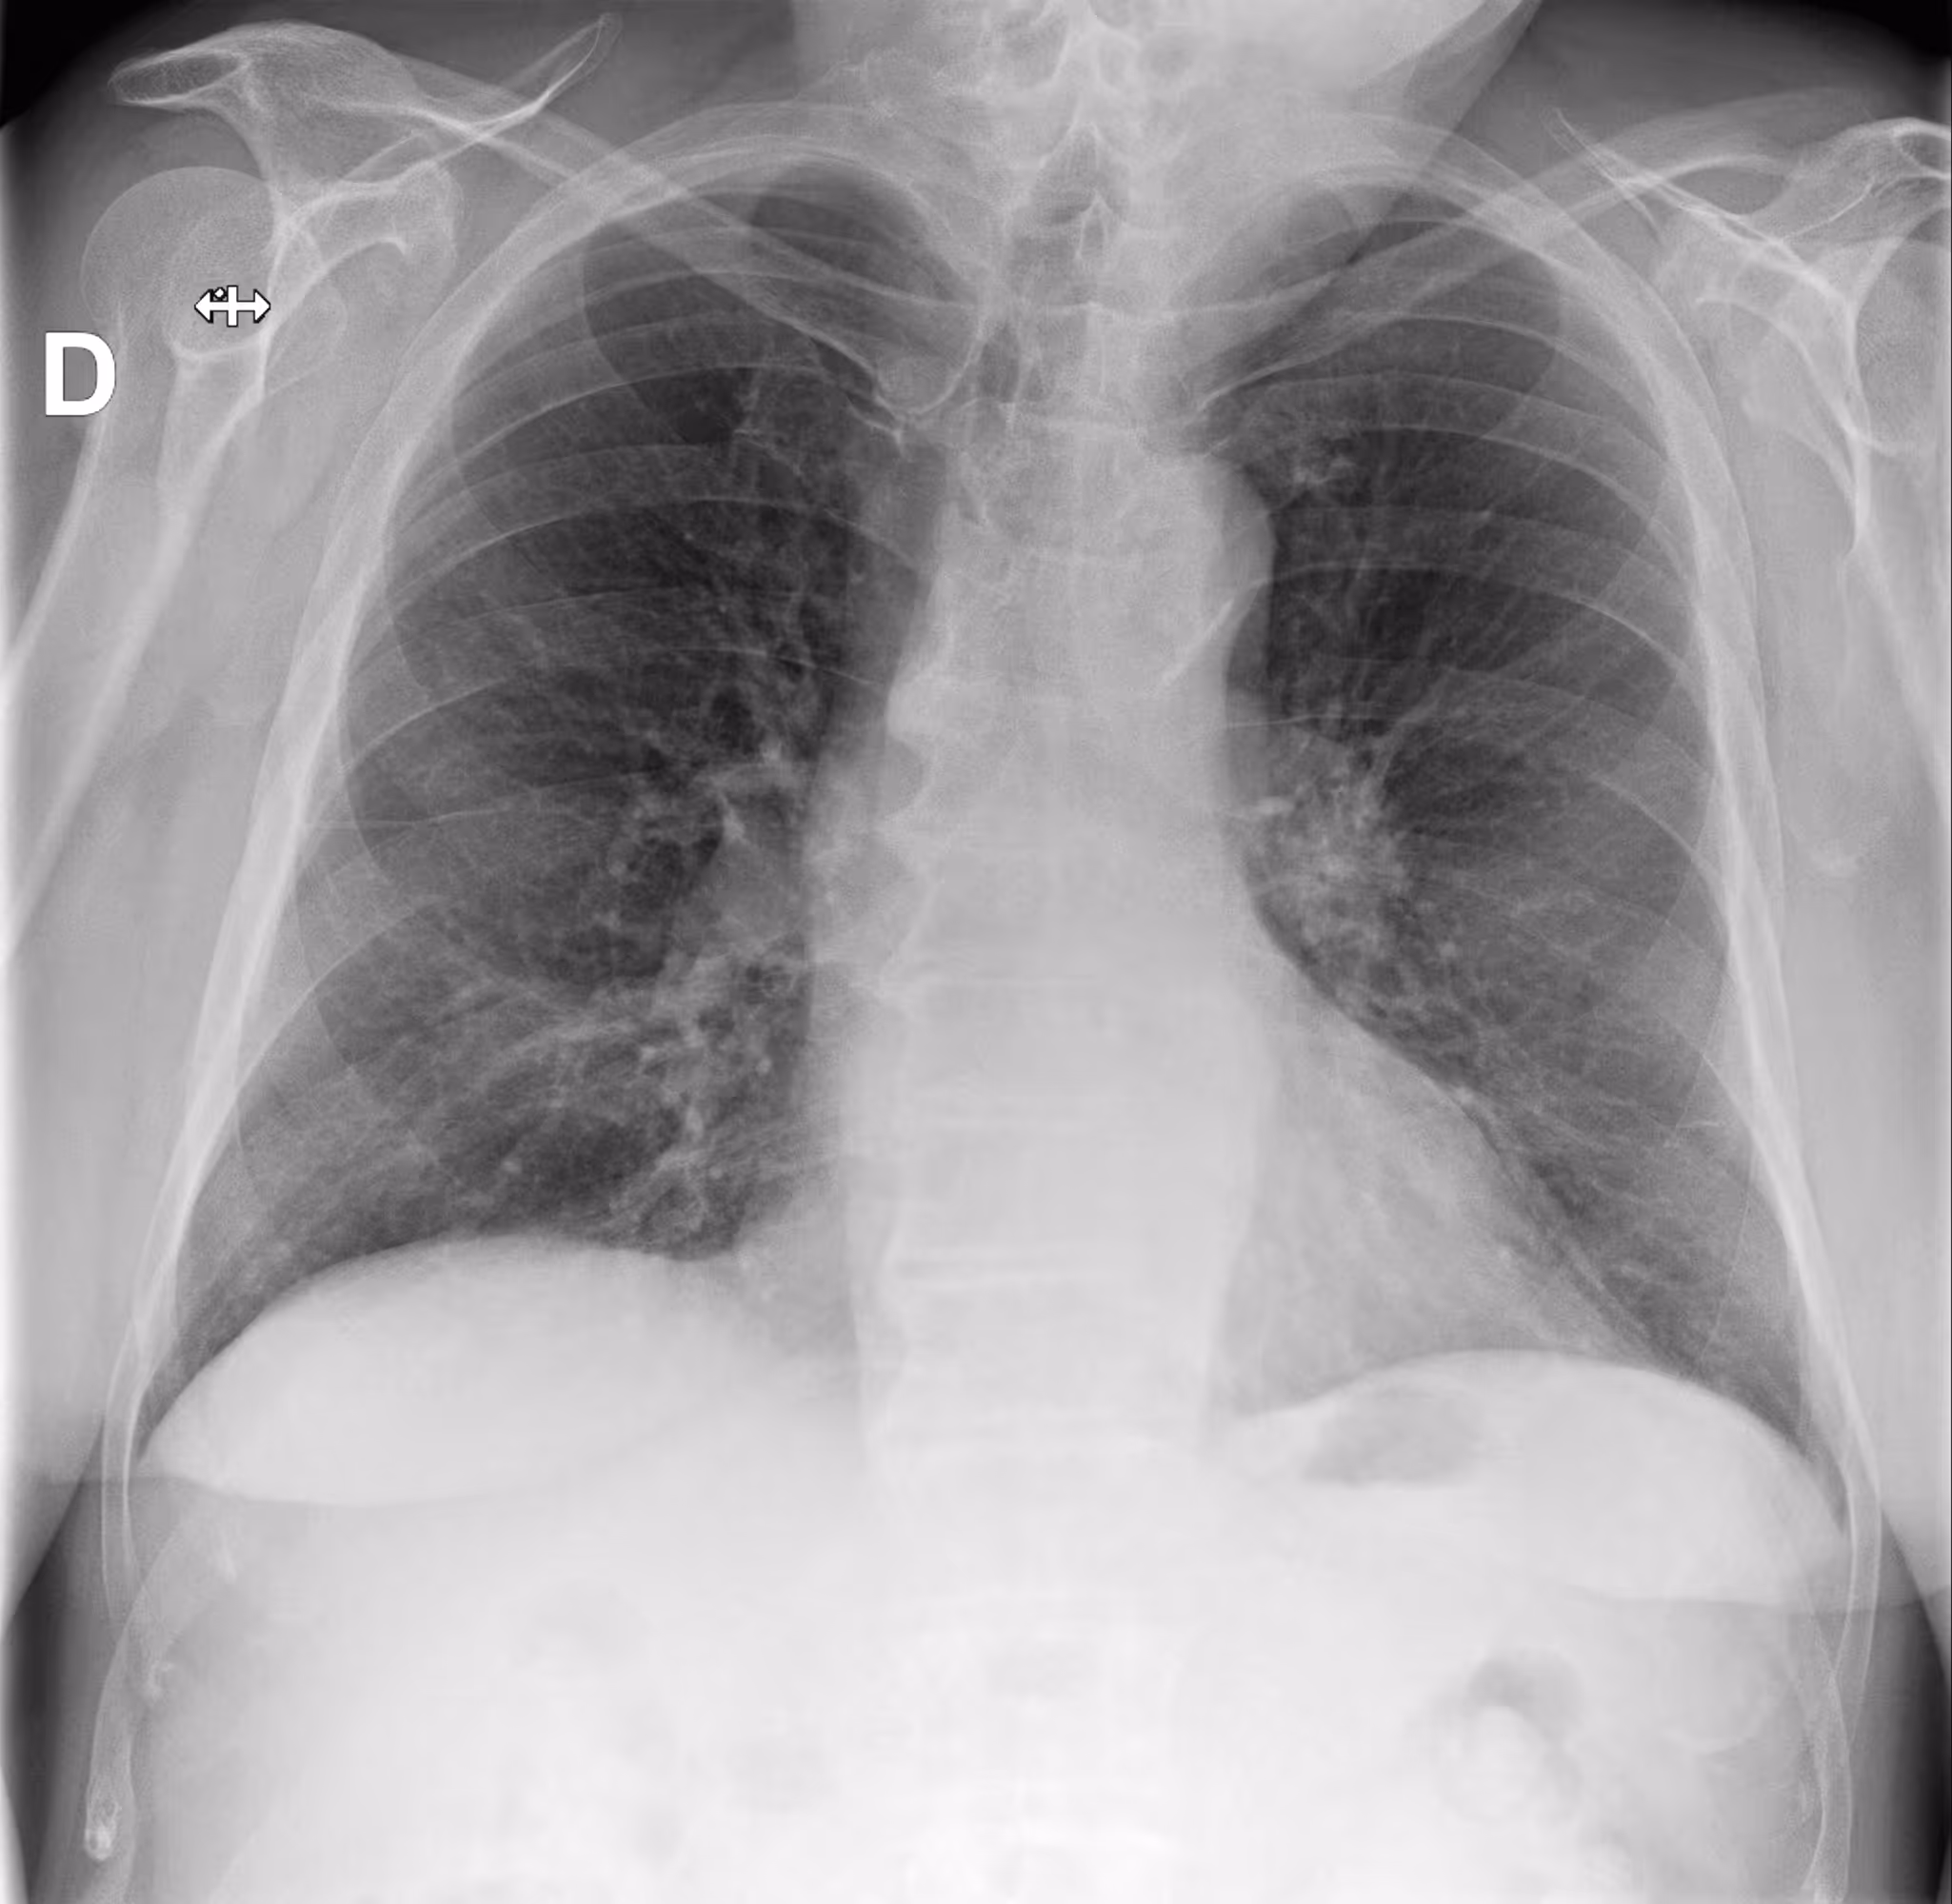

An 80-year-old male with a previously normal chest X-ray presents for CT evaluation 9 months later, which reveals findings suggestive of lung cancer.

Results

ChestView detected the mediastinal mass on the initial X-ray.